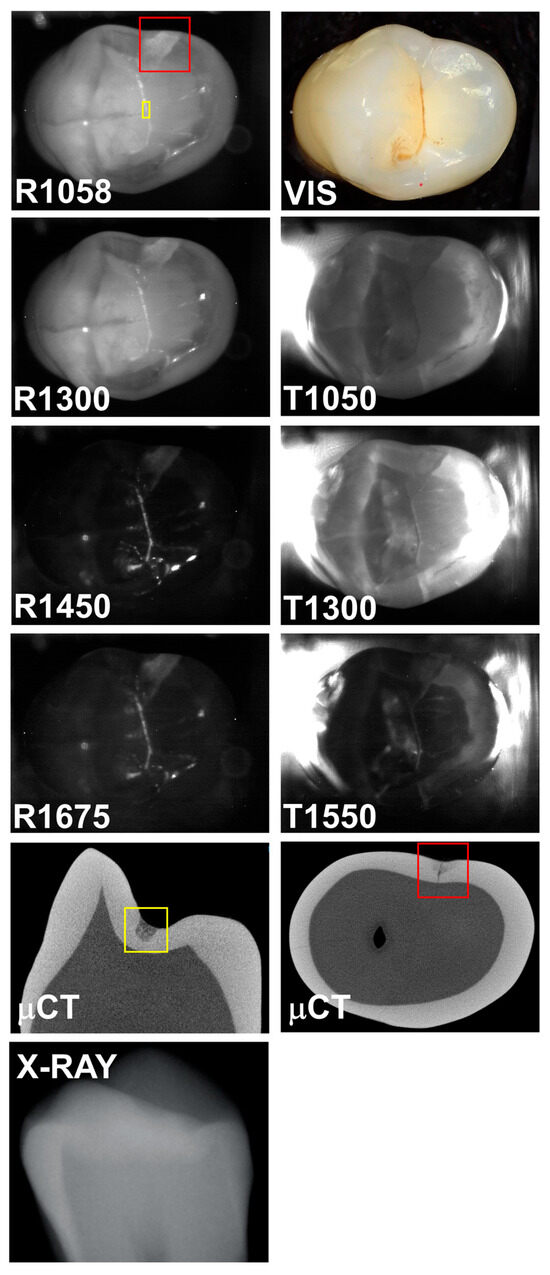

The seven SWIR occlusal reflectance and transillumination images are shown in Figure 2 for a tooth with an interproximal lesion that is not visible on the radiograph. The μCT image shows that it is a large lesion that penetrates into dentin. The lesion is clearly visible at all seven of the SWIR wavelengths with high contrast. It is not visible in the color image (VIS), i.e., at 400–700 nm. The contrast is highest for reflectance at 1450 nm where it is 0.81 and lowest at 1058 nm where it is 0.34.

Figure 2. SWIR occlusal reflectance (R) images at 1058, 1300, 1450, and 1675 nm along with SWIR occlusal transillumination (T) images at 1050, 1300, and 1550 nm are shown for a tooth with an occlusal lesion enclosed in the red box. A color (VIS) image, a slice extracted from the μCT image, and a radiograph (X-RAY) are also shown.

Reflectance at 1058 nm and 1300 nm was also included because it is also desirable to better visualize the surface of the tooth, and at longer wavelengths beyond 1400 nm the surface of sound areas of the tooth may not be visible due to the lower scattering of sound enamel and the increase in water absorption [4]. This is particularly challenging when surfaces are wet. Time-resolved SWIR reflectance imaging during the drying of lesions with forced air can be used to assess the activity of lesions [4], and it may be difficult to view the lesions to optimally position the imaging probe directly over the lesions being investigated. The use of a second reflectance wavelength may greatly aid alignment. In addition, image registration of the sequential images may benefit from the higher reflectivity, particularly at 1058 nm. The reflectance images shown in Figure 2, Figure 3 and Figure 4 clearly show the increased visibility of sound areas of the tooth compared to 1450 and 1675 nm.